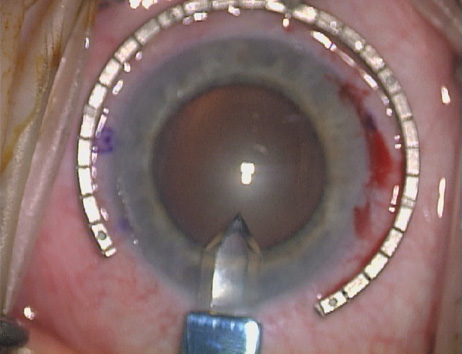

Case 1 is a 68-year-old male who presented for right cataract surgery. His refraction was −1.00 +2.25 × 80 and was recorded as reliable, consistent with his modest cataract density. Keratometry readings were 44.75 × 75 and 43.00 × 165. Corneal topography confirmed slightly more than 2.00 D of regular and slightly oblique cylinder. Consulting the nomogram, a plan was devised for a pair of LRIs to be centered over the 75-degree axis, with each incision delineating 45 degrees of arc. A single plane phaco incision was used and maintained at a size of less than 3.2 mm (Figs. 811).

Fig. 8. Steep meridian is confirmed intraoperatively by keratoscopy. In this left eye viewed from the temporal side, the “short axis” of the corneal mire is seen to be at the 75-degree meridian. (Reprinted from Hardten DR, Lindstrom RL, Davis EA. Phakic Intraocular Lenses: Principles and Practice. Thorofare, NJ: SLACK Incorporated, 2004, with permission.)